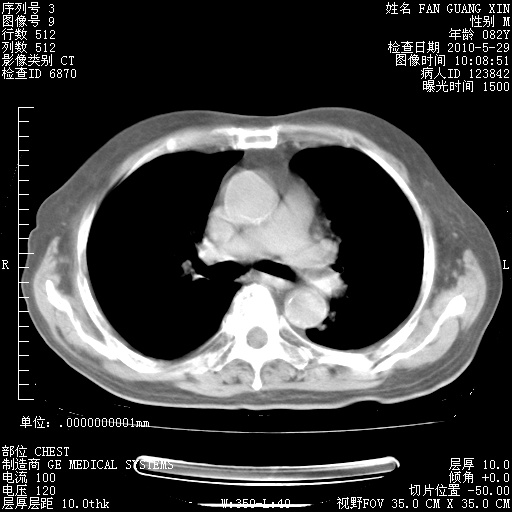

治疗3周后的肺部CT纵隔窗

再治疗10天后的肺部CT

再治疗10天后的肺部CT 纵膈窗

阅读此次胸部CT,肺间质渗出性改变较入院时有吸收。目前从体温、白细胞、中性分叶明显增高,肯定存在细菌感染(发生医院感染哦,若无消化道及泌尿系统等感染的依据,肺部感染可能大)。若你院头孢哌酮舒巴坦钠耐药率较高,同意你的方案,若48小时体温仍高,可考虑使用碳青霉稀类抗菌药物,同时可予超声雾化、注意滴数时加大液体量。白蛋白33.30g/L较低哦,需加强营养等支持治疗。